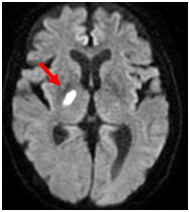

MRI;拡散強調画像

【MRI;拡散強調画像】

MRIでは1.5cm以下の小さな梗塞として描出。